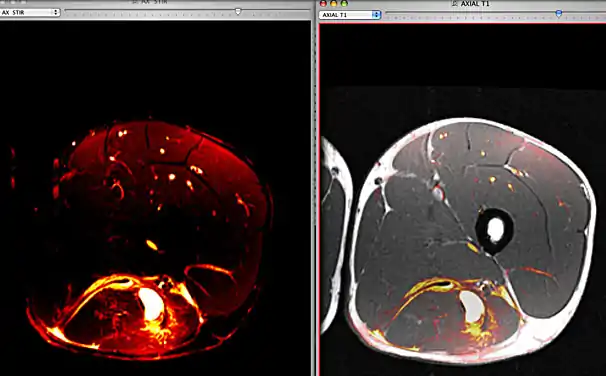

Fusion image between axial STIR and T1 images of a football player with a hamstring hematoma. These images were performed during the same imaging exam and were automatically aligned by OsiriX.